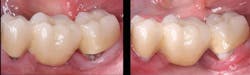

Finish and polish the new resin crown, and seat it with a resin-modified glass ionomer cement

When finishing, be very careful to leave the margins intact. This is the final crown for the patient (figure 6)!

Figure 6: The finished and polished resin crown has been cemented with resin-modified glass ionomer cement to take advantage of the cariostatic characteristics of that cement-in this case, the popular 3M RelyX Luting Plus was used.